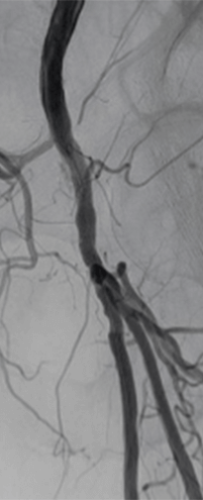

Results

Final angiography showed complete revascularization of the femoropopliteal segment without dissection and fast runoff to the foot (Figure 2).